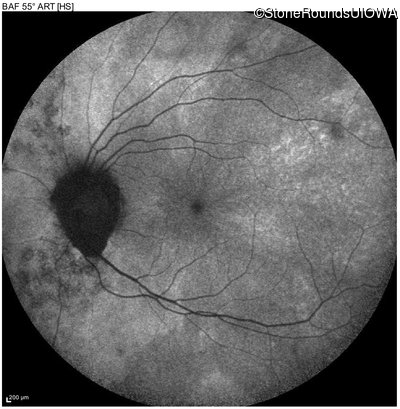

Blue Autofluorescence - Left - 20/20 -1

Exemplar